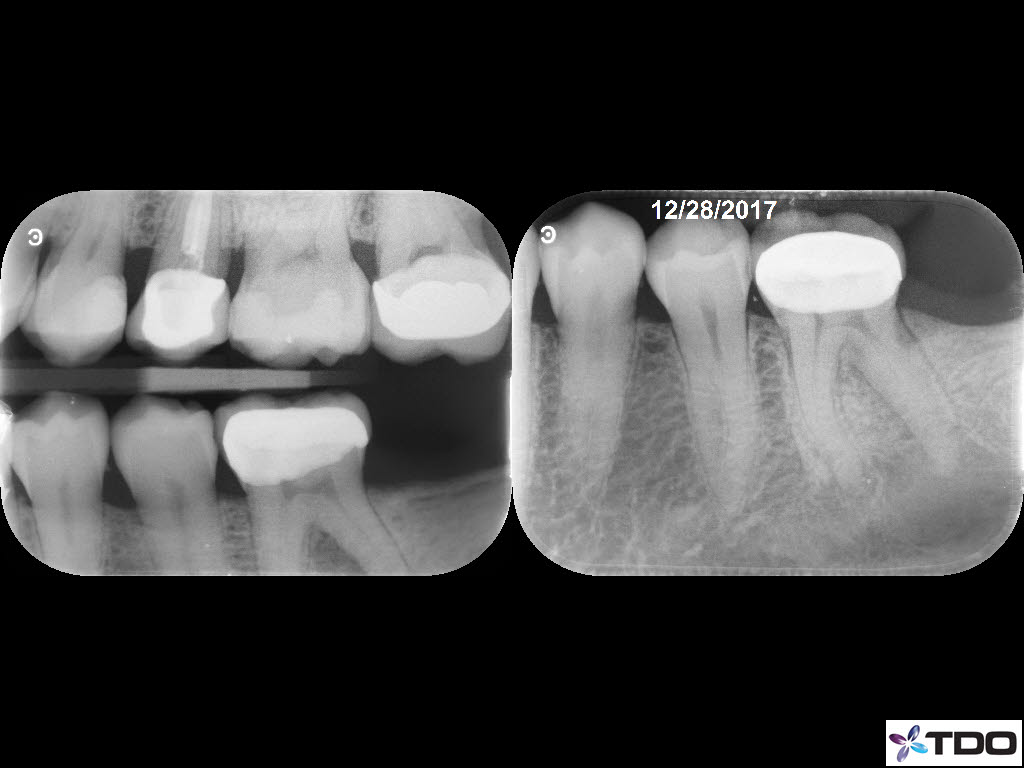

50 yof

Necrotic Pulp. Symptomatic AP. 3 visits due to persistent drainage from the DL at the second visit two weeks later. Let the tooth sit in calcium hydroxide over one month before completing. Tooth was asymptomatic and dry canals at the third visit.